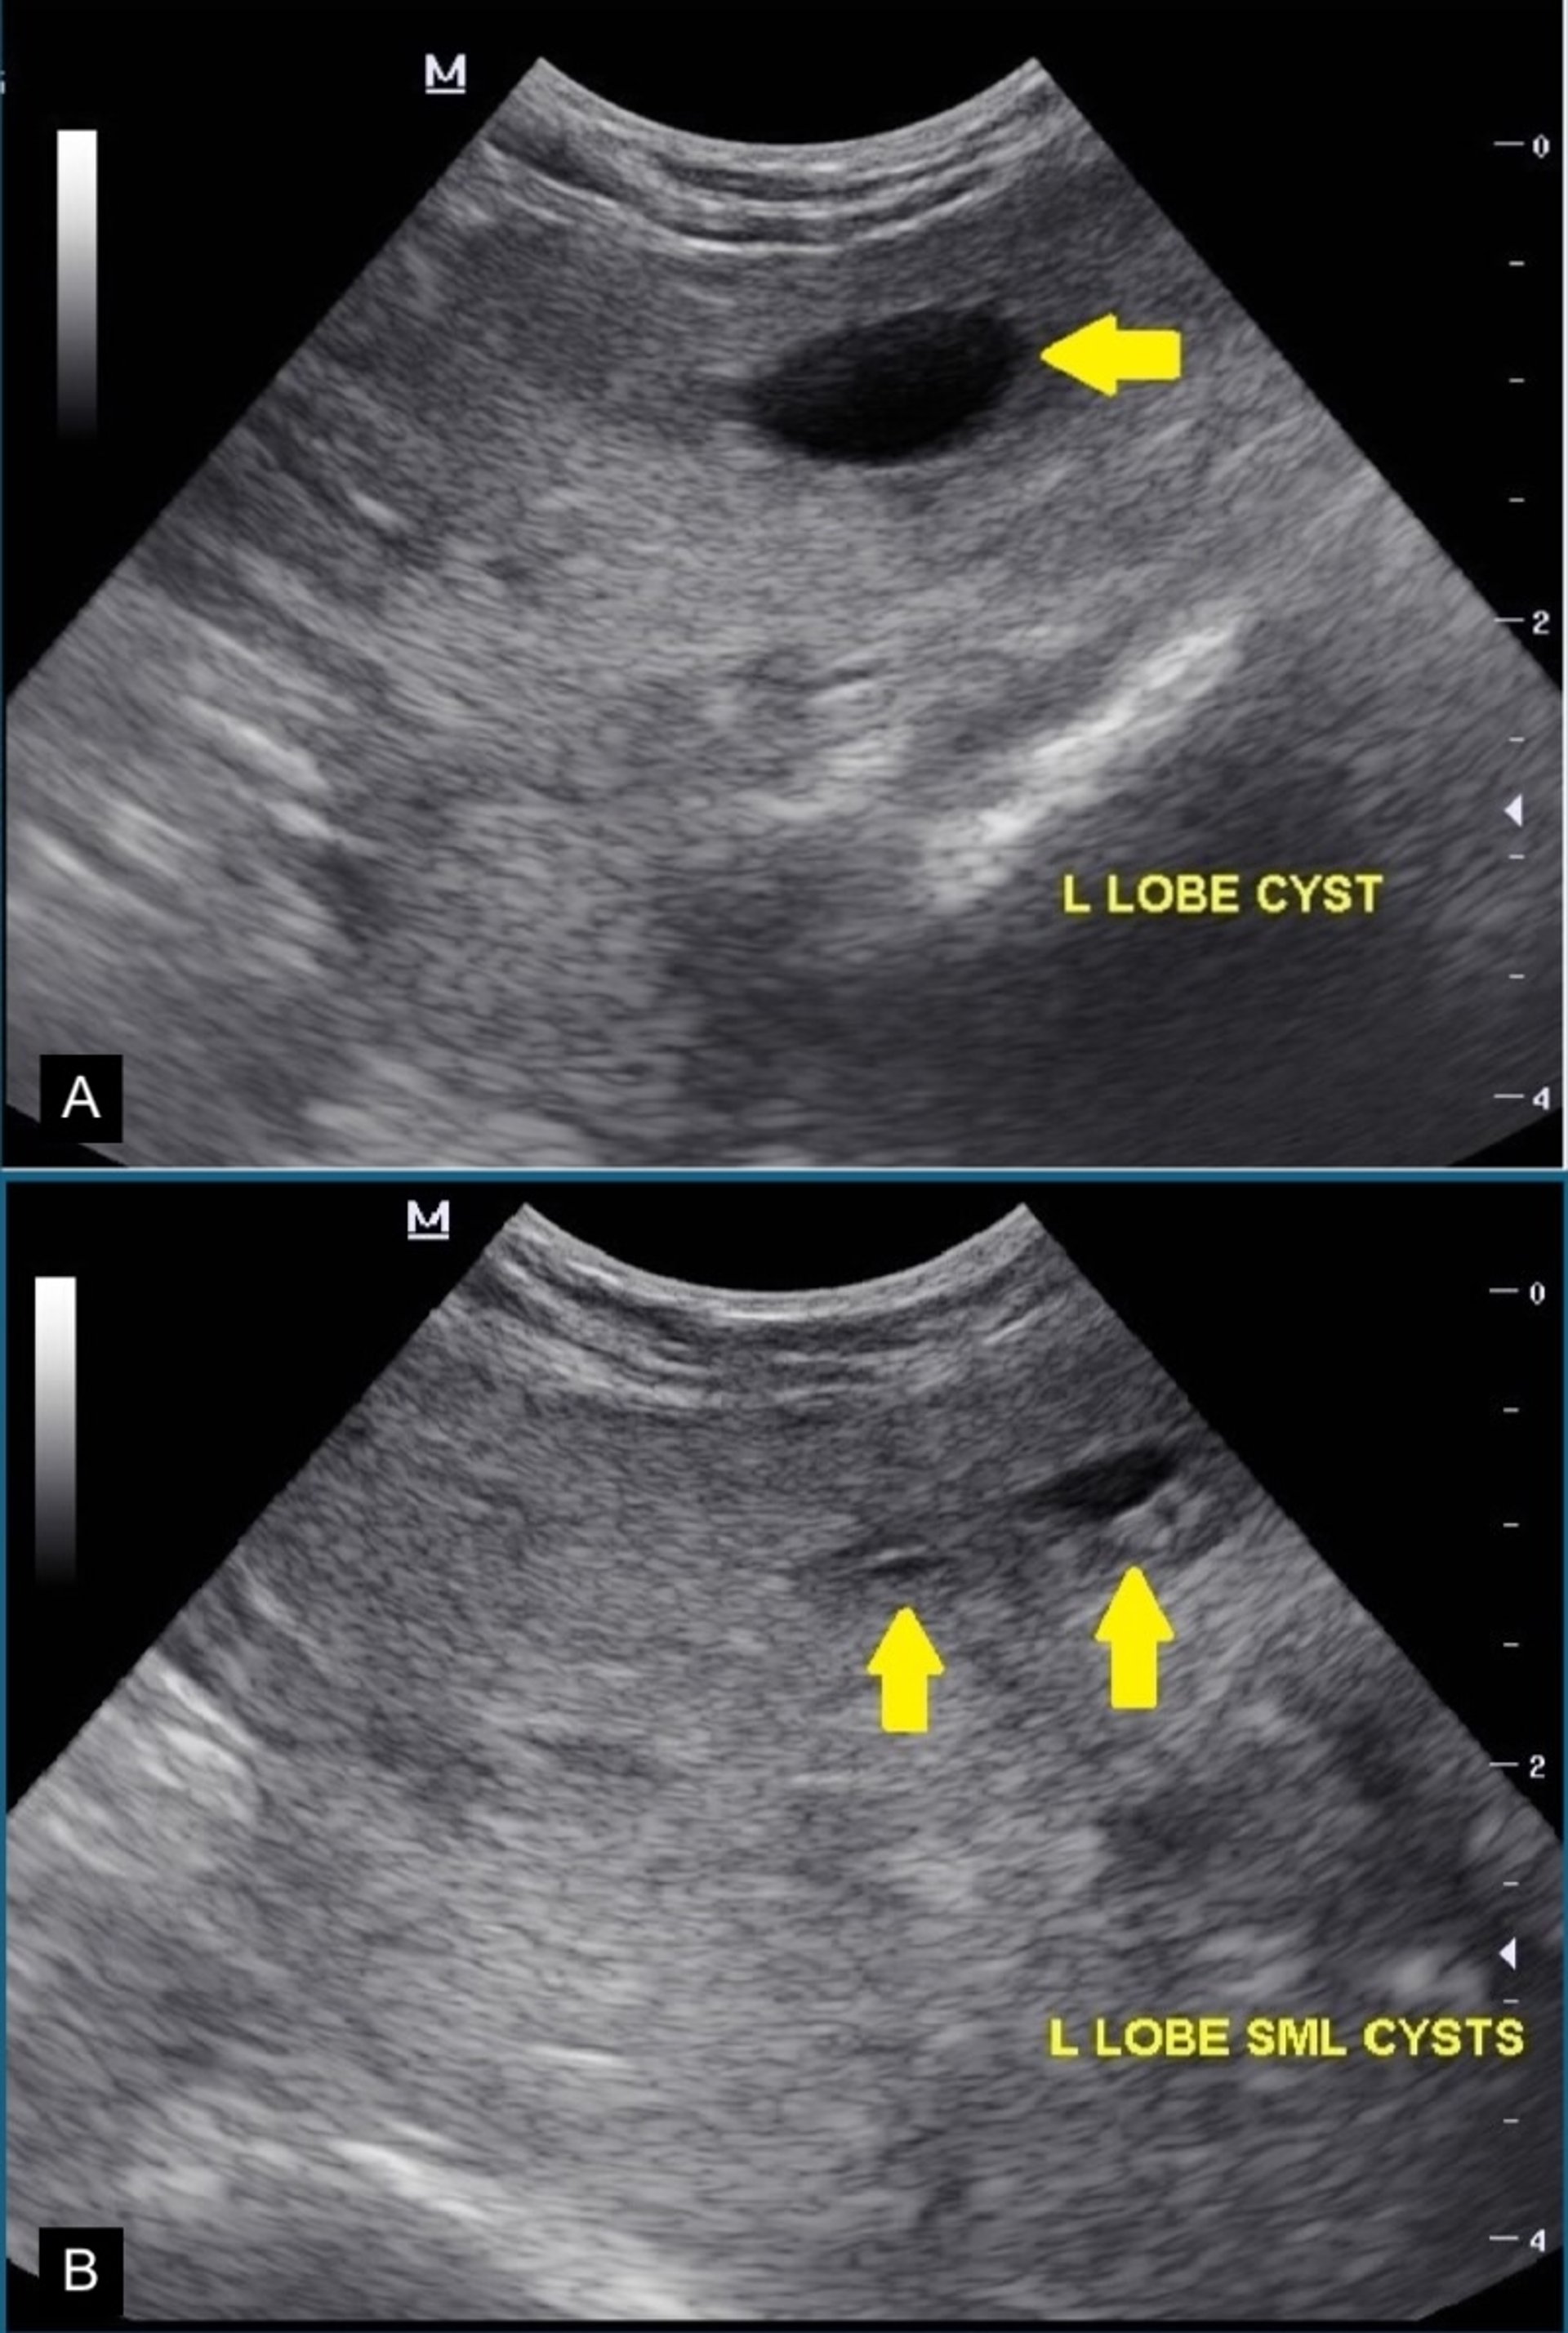

Cystic benign prostatic hyperplasia, transabdominal ultrasonography, dog

Transabdominal ultrasonographic images of the prostate of a dog with cystic benign prostatic hyperplasia. The prostate has a heterogeneous echotexture and irregular margins. Hypoechoic to anechoic, thin-walled intraparenchymal cysts (yellow arrows) are visible within the prostate.

Courtesy of Dr. Michelle Kutzler.